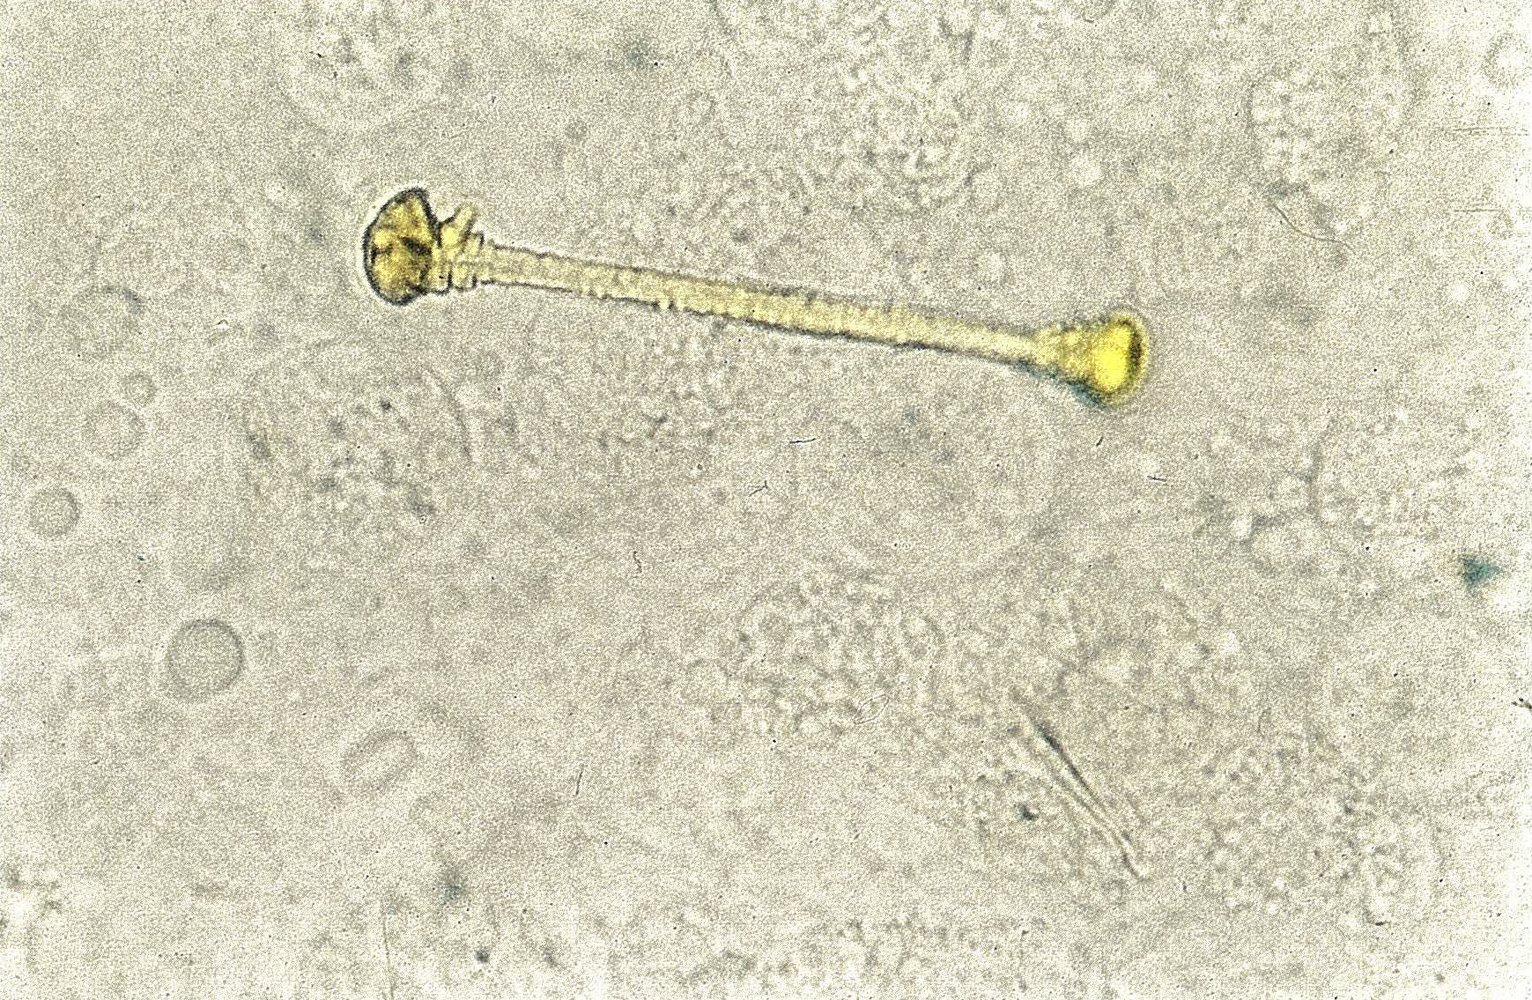

• Bronchoalveolar lavage

• Microscopic asbestos bodies (a type of ferruginous body)

• Dumbbell-shaped, golden-brown fusiform rods surrounded by an iron protein coat [3]

• Stain positive with Prussian blue [6]

• Occasionally also found in alveolar sputum samples [6]